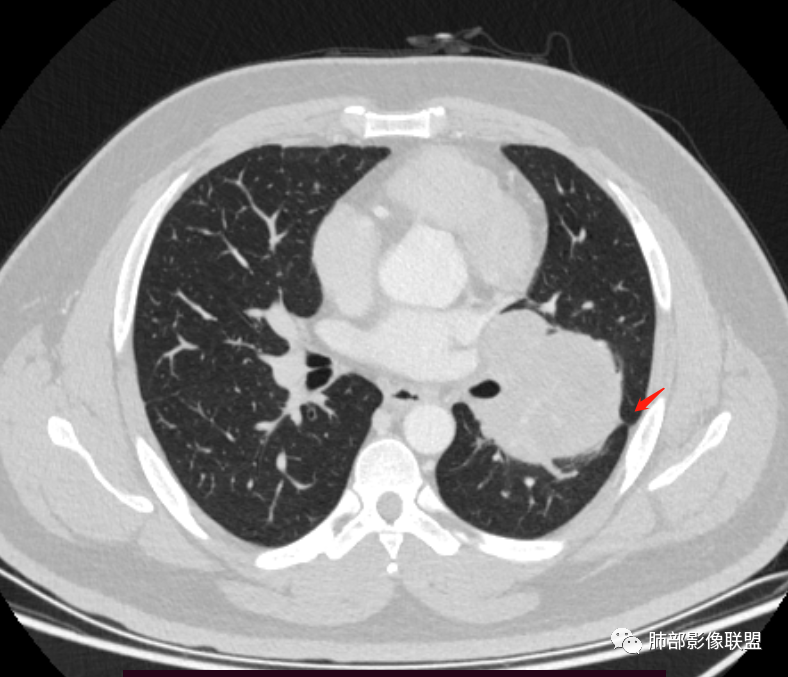

青年人,左肺下叶占位,边界清晰,支气管受包埋,病灶可见空气半月征,增强病灶内见血管影,纵膈未见增大淋巴结,考虑交界性肿瘤性病变,PSP,SFT,其次肉瘤类,鉴别淋巴瘤,小细胞癌。

左肺下叶巨大肿物,边缘光滑,支气管截断,蛇纹血管征?肿物远端可见空气新月征,恶性SFT ?肉瘤?

青年男性,体检发现,左肺下叶肿块,边界清晰,支气管受压,病灶可见空气半月征,增强不均匀强化,内见血管穿行影,定位胸膜起源,PSP?SFT?肺内肉瘤类待排。

青年男性,体检发现左肺不规则类圆形占位性病变,叶间裂区域,定位胸膜来源。左肺下叶支气管受压狭窄,但管壁光整,未见腔内阻塞或管壁受侵。包块边界清晰,浅分叶,内部密度不均匀,病灶后份见空气新月征。渐进性强化,增强动脉期见分支状血管,蛇纹血管征。肺门纵膈未见增大淋巴结,符合孤立性纤维瘤(SFT)。